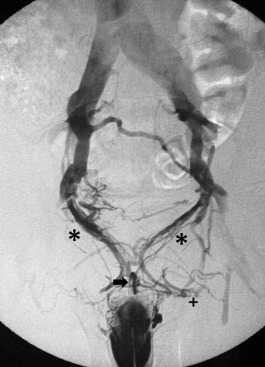

Кавернозография

Динамическая кавернозография - это диагностический тест, направленный на изучение причин веногенной эректильной дисфункции, и проводится при исключении других причин слабой потенции у молодых пациентов. Венозная утечка из эрегированного полового члена может развиться по разным причинам. Чаще всего это врождённое состояние или следствие тазовой венозной гипертензии (варикоцеле). При веногенной импотенции эрекция возникает, но она нестойкая, что не позволяет завершить половой акт. После выявления причин эректильной слабости у доктора появляется объект лечебного воздействия - несостоятельная вена, которую можно закрыть и улучшить эрекцию.

Как проводится кавернозография

Обследование проводится в кабинете цифровой субтракционной ангиографии. Во время исследования пациент находится в положении лёжа на спине. С целью обезболивания проводится проводниковая анестезия с введением у основания полового члена 10 мл 2% лидокаина. Затем основание пениса передавливается тонким резиновым жгутом.

Для стимуляции эрекции вводится 2 мл (в дозе 10 мкг простагландина Е1) вазапростана в пещеристое тело по боковой поверхности очень тонкой иголочкой. Затем напротив этой иглы пунктируется такой же иглой другое пещеристое тело и к игле, через удлинитель присоединяется специальный манометр. После этого проводится дополнительная пункция иглой для забора крови (21G) в средней части правого кавернозного тела и игла соединяется с инфузионным насосом для введения контраста.. Важно отметить, что игла должна хорошо фиксироваться на половом члене.

Ход исследования

В процессе подготовки к выполнению кавернозографии сначала проводится измерение давления в пещеристых телах. В расслабленный пенис через инъекционный насос вводится 60 мл физиологического раствора + 20 мл контрастного препарата со скоростью 0,4 мл / с. Через 10 минут наступает эрекция полового члена. С целью визуализации заполнения кавернозных тел с боковых и прямых проекций после введения контраста выполняются рентгеновские снимки. При достижении интракавернозного давления в 150 мм.рт.ст. нагнетание раствора уменьшали до 0,1 мл в секунду для поддержания хорошей эрекции. При снижении артериального давления в пещеристых телах выполняли кавернозографию на фоне увеличения скорости инфузии.

Такой метод имитировал естественную эрекцию, а её ослабление в процессе исследования позволяло выявить наличие различных патологических венозных сбросов. Такая кавернозография даёт достаточно информации о венозных утечках, однако существует риск развития приапизма, а контрастирование дорсальной вены полового органа позволит определить эти утечки без необходимости интракавернозных инъекций. Однако прямая кавернозография необходима для выявления изменений органической структуры пениса при болезни Пейрони и разрывов в кавернозных телах.